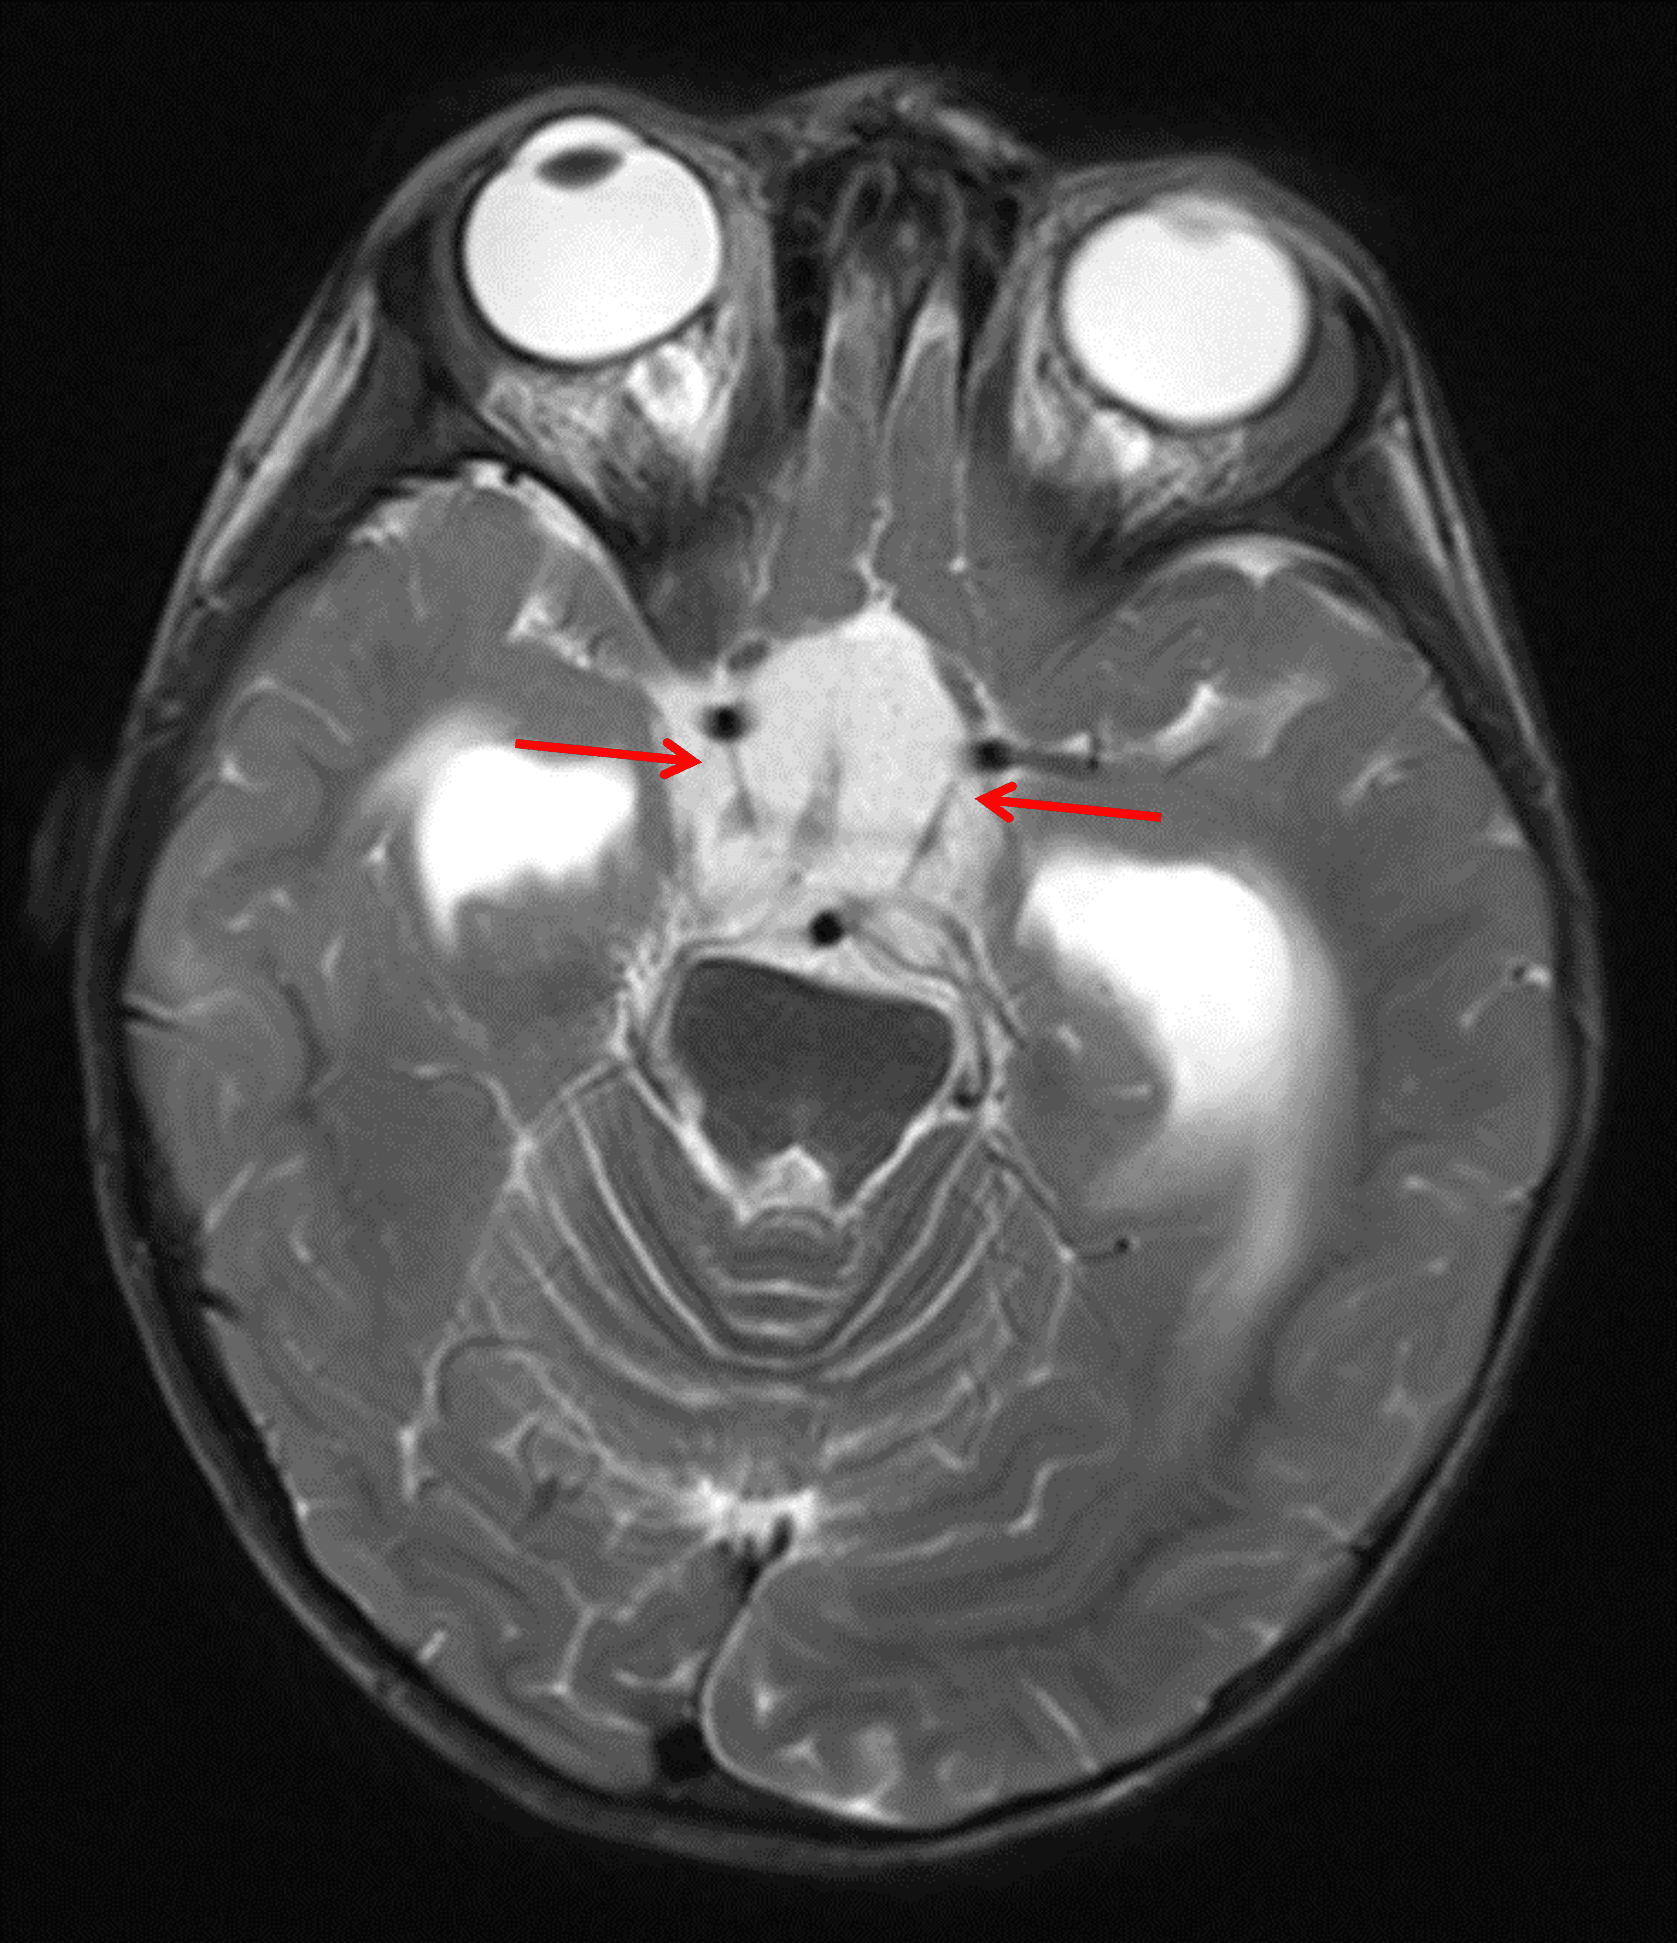

Markedly T2 hyperintense mass centered in the suprasellar cistern (red arrows).